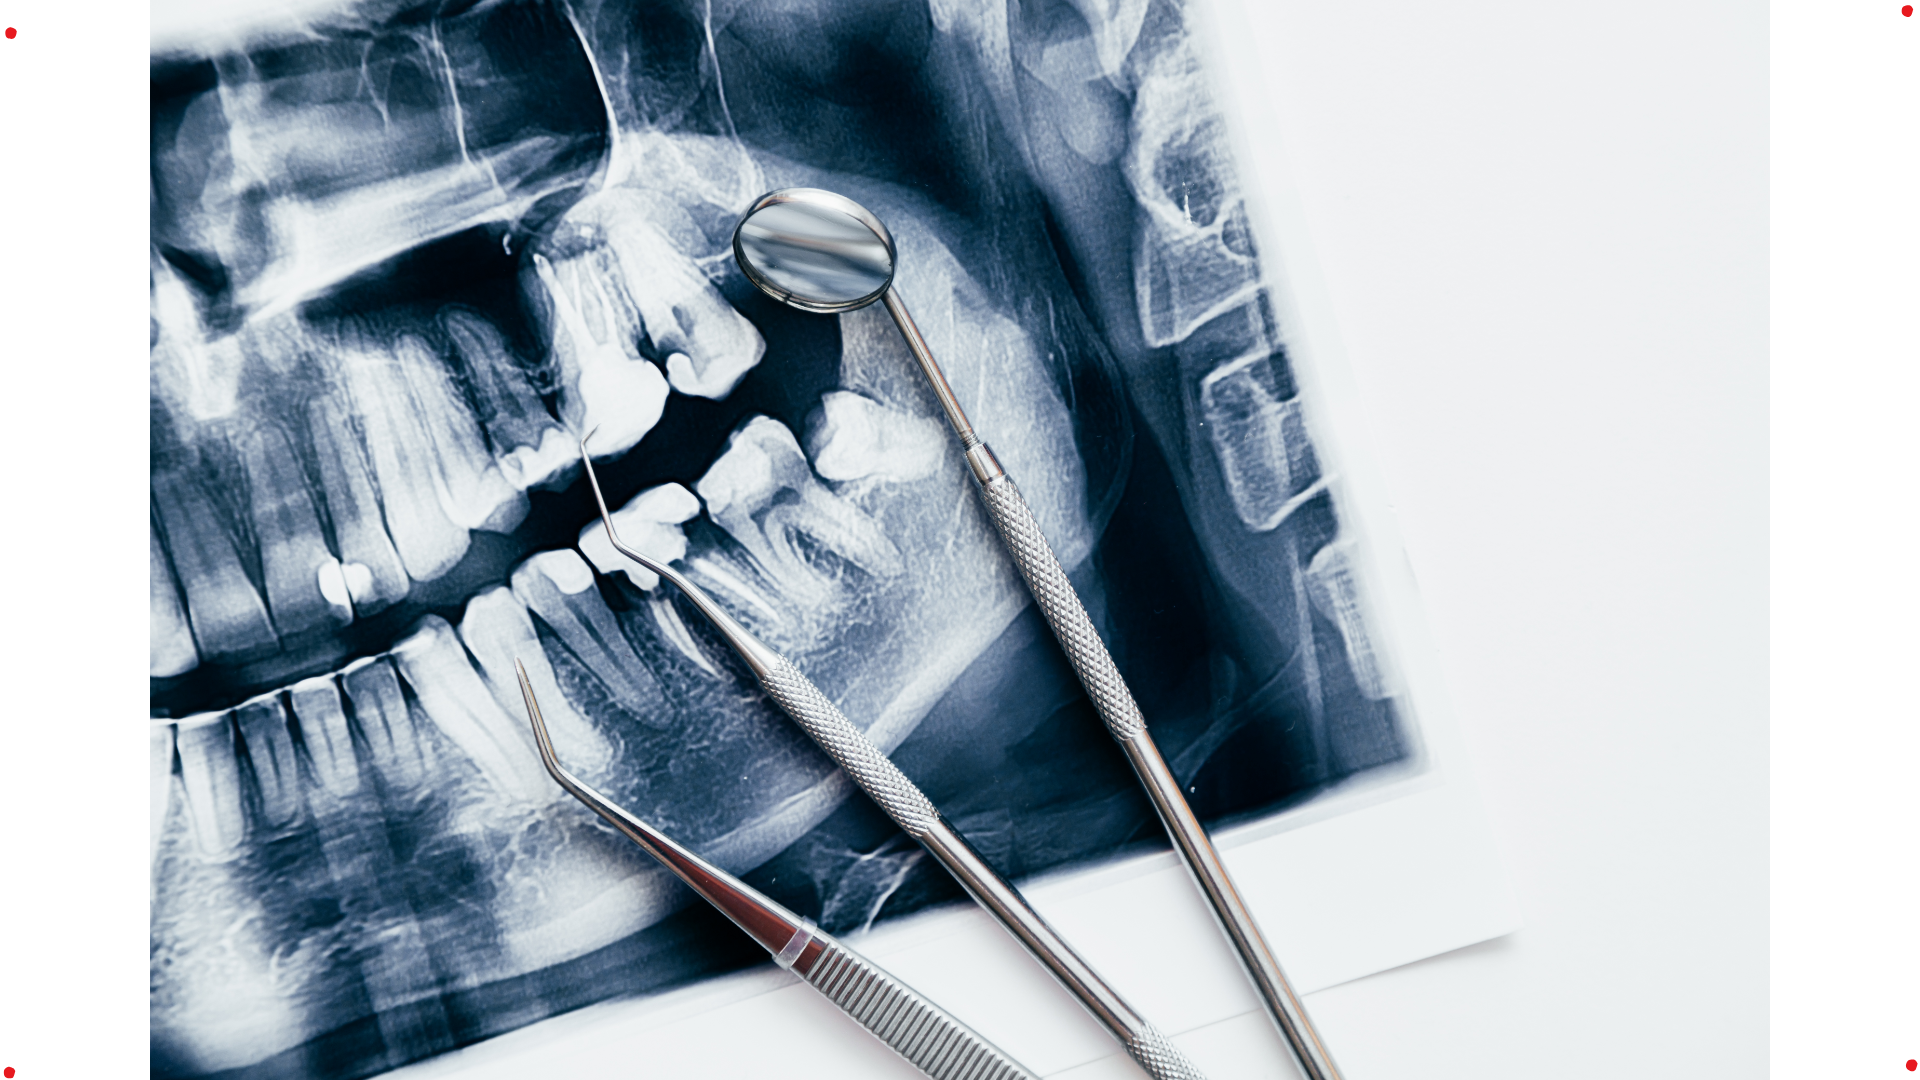

At Cuspid Dental, full mouth rehabilitation begins with a comprehensive diagnostic evaluation focused on function, jaw position and long-term stability—not isolated dental problems. Each stage of treatment is guided by diagnosis and functional analysis, ensuring predictability rather than short-term fixes.

• Comprehensive oral and functional examination, including digital imaging, diagnostic records and bite & jaw assessment .

✔ Advanced Diagnostic & Planning Protocols – Use of digital imaging, articulated models, and functional analysis to plan restorations that respect jaw position, bite dynamics and long-term stability.